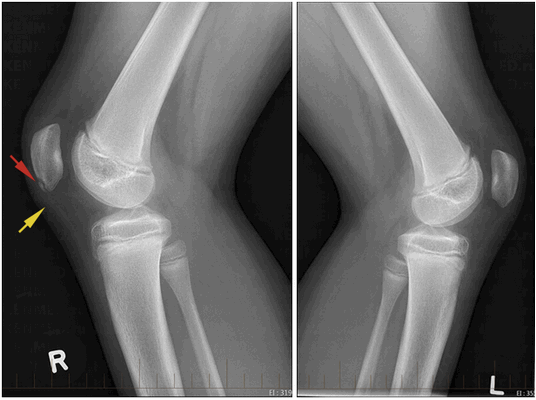

Рентгенография коленных суставов (сагиттальный снимок): в нижнем полюсе правого надколенника видна зона оссификации проксимальной части связки надколенника (красная стрелка), желтой стрелкой отмечено утолщение связки. Левый коленный сустав без патологии

- Рентгенография.

- На ранних стадиях заболевания малоинформативна.

- При хроническом течении: возможно выявление зон кальцификации/оссификации (окостенения) проксимальной (верхней) части связки надколенника; вначале оссификация фрагментарная, со временем оссификаты могут сливаться друг с другом и/или с нижним полюсом надколенника (при этом полюс увеличивается в размерах); сама связка надколенника утолщается.